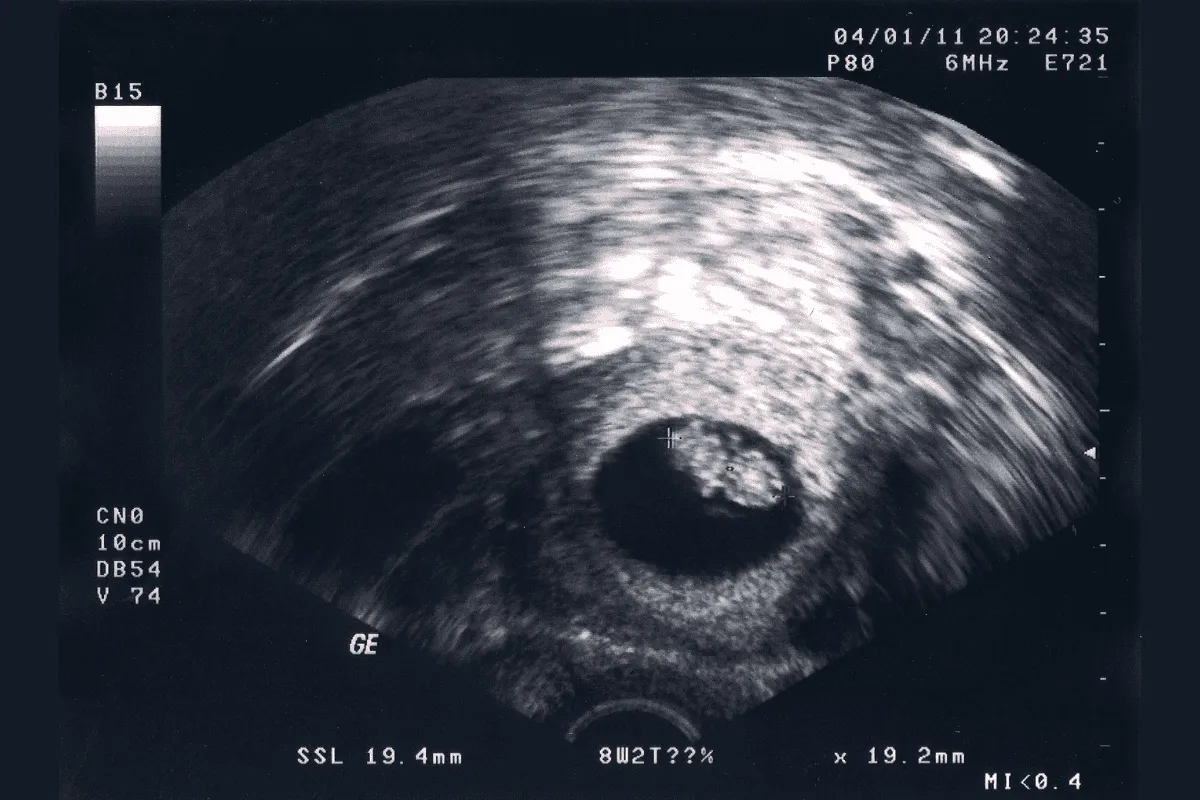

Siêu âm ở tuần thai thứ 8

Khi tiến hành siêu âm thai, mẹ bầu có thể được chỉ định siêu âm qua thành bụng hoặc siêu âm đầu dò ngả âm đạo.

- Siêu âm qua thành bụng: Để thực hiện phương pháp siêu âm này, mẹ phải nhịn tiểu trong khoảng thời gian nhất định để bàng quang căng đầy giúp đẩy tử cung lên cao. Điều này giúp bác sĩ siêu âm dễ dàng quan sát thai nhi.

- Siêu âm đầu dò: Phương pháp này đem lại kết quả chính xác hơn và thường được thực hiện khi bác sĩ nghi ngờ thai trong khoảng tuần thứ 6 – 8 không có tim thai hoặc có những bất thường khác.

- Theo dõi lịch khám định kỳ: Ở tuần thai thứ 8, đây có thể là lần khám thai thứ 2 hoặc thứ 3 của mẹ bầu. kiểm tra toàn diện hơn, bác sĩ sẽ siêu âm xác định tim thai, các vấn đề của phôi thai, nếu trong lần đầu đi khám, cái thai quá nhỏ bác sĩ chưa xác định được.